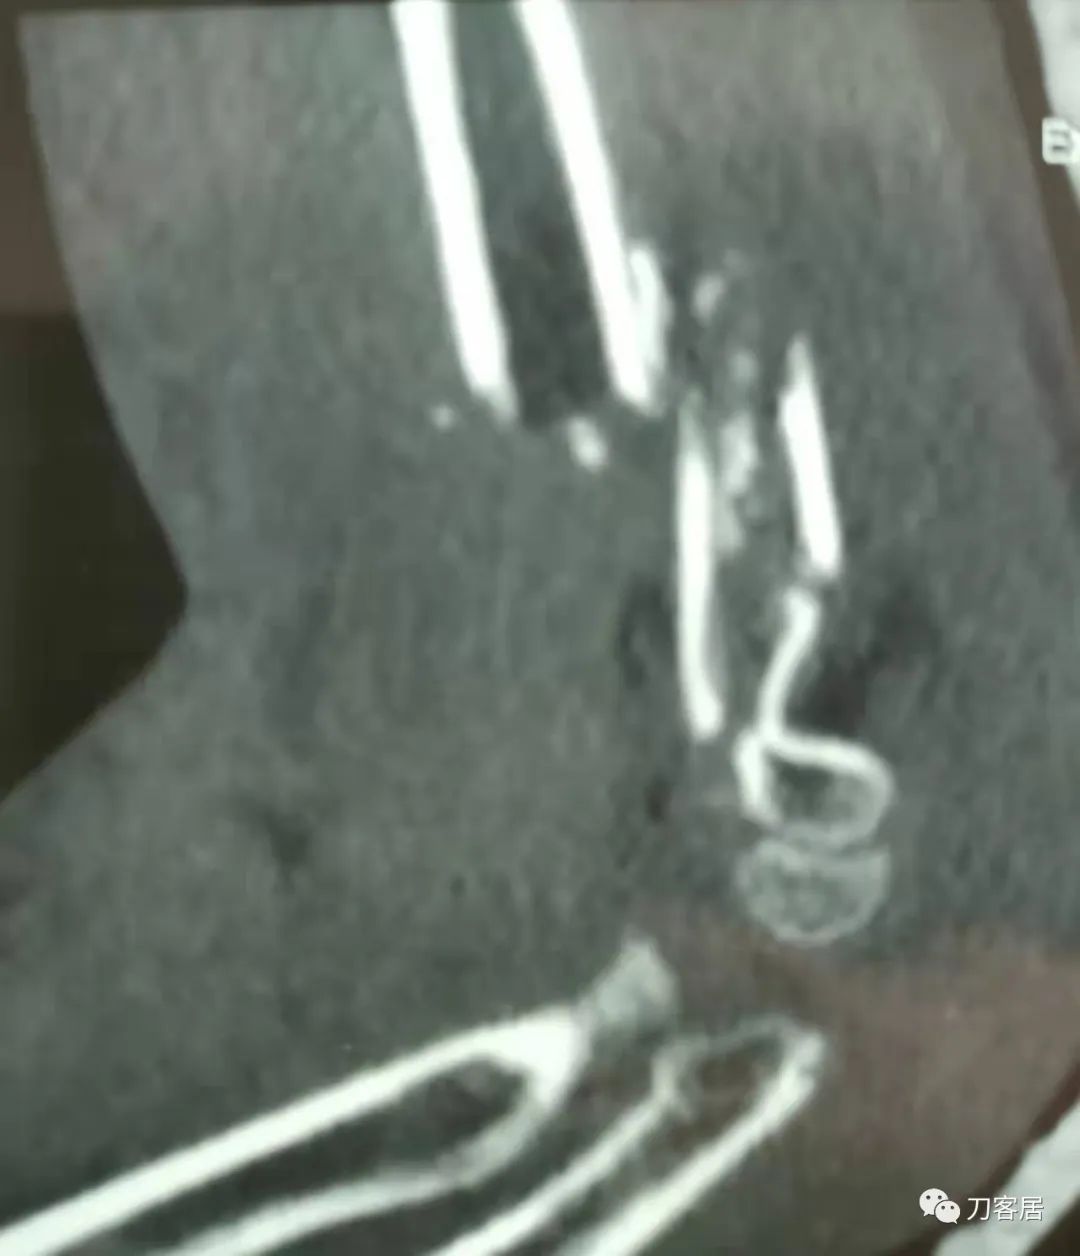

20210921当地县医院CT01

20210921当地县医院CT02

20210921当地县医院CT03

20210921当地县医院CT04

20210921当地县医院CT05

20210921当地县医院CT06

20210921当地县医院CT07

20210921当地县医院CT08

20210921当地县医院CT09